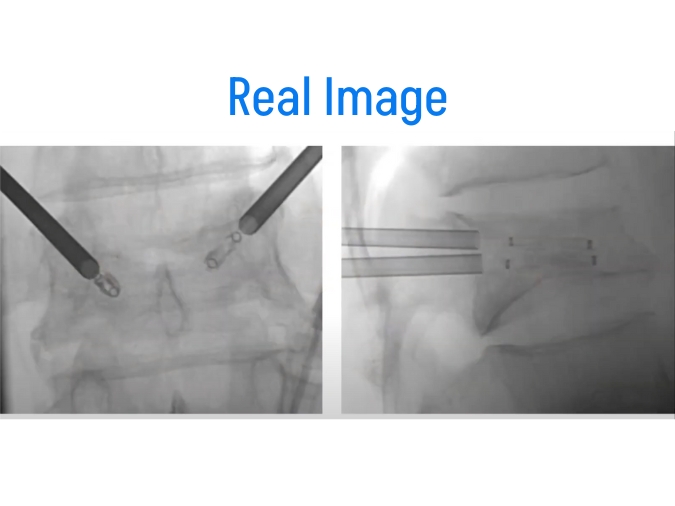

Vertebroplasty and kyphoplasty are both minimally invasive procedures performed under fluoroscopic guidance to treat vertebral compression fractures. These fractures typically occur in the thoracic (mid-back) or lumbar (lower back) regions of the spine and can cause severe pain and disability. Both procedures involve the injection of bone cement into the fractured vertebra to stabilize the fracture and alleviate pain. While similar in principle, there are some differences between vertebroplasty and kyphoplasty in terms of technique and outcomes.

- Procedure: The procedure is performed by an interventional radiologist or spine surgeon. Using fluoroscopic guidance, a small incision is made in the skin, and a needle is advanced into the fractured vertebra. In vertebroplasty, bone cement is injected directly into the vertebra. In kyphoplasty, the balloon is inserted and inflated to create a cavity before injecting the cement.